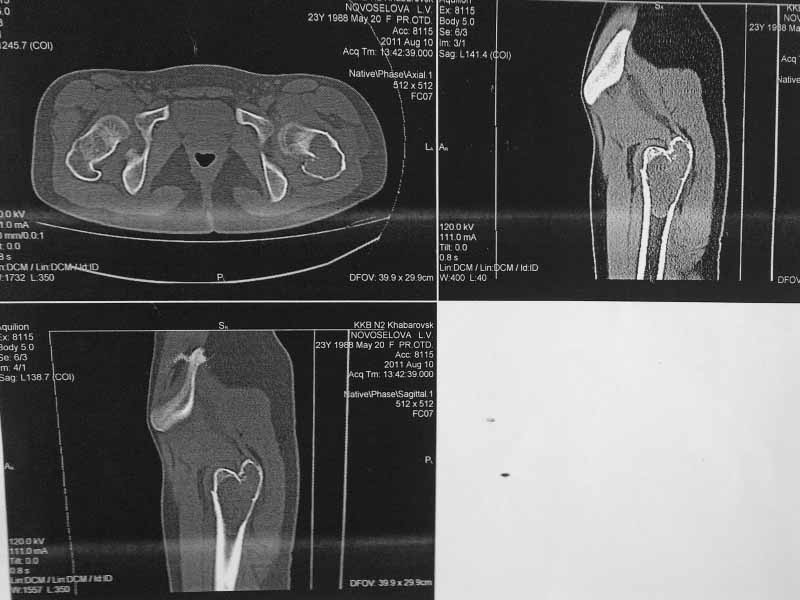

Молодая пациентка 23 лет. Травма в результате падения с высоты своего роста.

Упала 2 дня назад, доставлена к нам вот с такой картиной. Из анамнеза - боли

беспокоят в течении полугода, постоянные. Никуда не обращалась. Уважаемое сообщество

подскажите - ОБК?, Фиброзная дисплазия?, Киста?. Тактика ведения?. Девушка молодая!!!